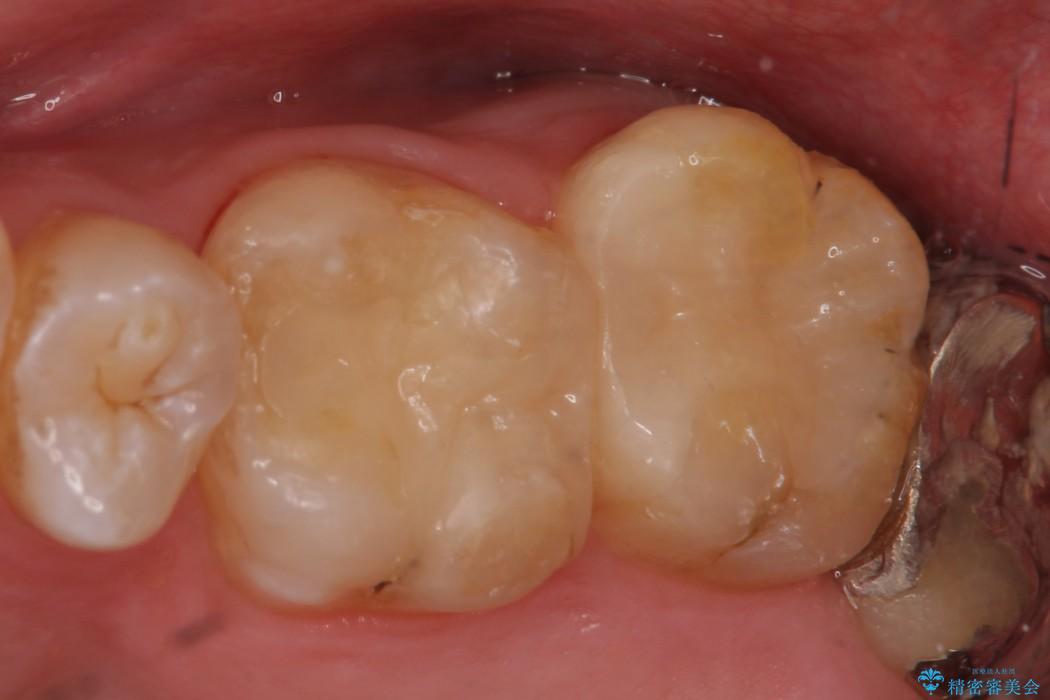

古い詰め物を外し、白く審美性の高いセラミックインレーにて再治療を行うこととしました。

今回は保険で治療してあった銀歯を審美性からセラミックインレーにて再度治療しました。

セラミックスは、見た目の審美性だけでなく劣化がしにくいことや金属アレルギーのリスクがないことがメリットとしてあげられます。